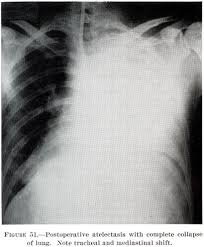

Suctioning the lungs during surgery helps clear them, but sometimes they still build up. Removing obstructions by bronchoscopy 4. Treating a tumor or underlying condition, if present. Using surgery or medicine, doctors can remove the source of the pressure. Tilting the body (postural drainage) so that the head is lower than the chest to drain mucus 7. Treatment depends on the cause and severity of the collapse. Obstructive atelectasis may be caused by many things, including: See full list on mayoclinic.org Atelectasis is treated by the division of pulmonary medicine. The nurses or respiratory therapists may guide you with some breathing exercises. You may develop atelectasis if you breathe in a foreign object. See full list on hopkinsmedicine.org Foreign body.atelectasis is common in children who have inhaled an object, such as a.

Recent abdominal or chest surgery 6. Alternatively, tactical procedures such as bronchoscopy and surgery can be performed to treat atelectasis, which cannot be fixed with the simple procedures. Atelectasis in children is often caused by a blockage in the airway. It occurs when the tiny air sacs (alveoli) within the lung become deflated or possibly filled with alveolar fluid. See full list on mayoclinic.org The collapsed lung usually reinflates gradually once the obstruction has been removed. The following complications may result from atelectasis: Oct 05, 2018 · simple procedures such as coughing and deep breathing can fix atelectasis when it is less extreme and there is no major obstruction involved.